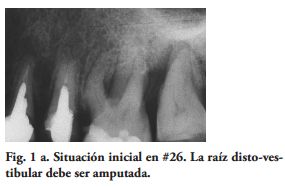

Al momento del examen, 10 (90.9%) EC estaban en función en 10 pacientes. Un molar 26, restaurado con EC, se perdió por enfermedad periodontal después de 12 años y 9 meses en función. Ninguna restauración se desprendió, no hubo recidiva de caries y al examen radiográfico no se observaron lesiones patológicas en los 10 DPET en función (Figs. 1a,1d; 2c; 3c,3d; 4c).

Las paredes internas de la corona dentaria y de la cámara pulpar, deben tener una divergencia hacia oclusal mayor de 60 y si presentan depresiones o zonas retentivas, deben rellenarse con cemento de ionómero de vidrio. El operador, dispensa una fina capa del mismo cemento en el piso cameral. En este estudio cuatro preparaciones tenían 3 paredes coronarias (Figs. 1b, 2a), cuatro 2 paredes (Fig. 3a) y en 2, las restauraciones abarcaban 4 paredes coronarias.